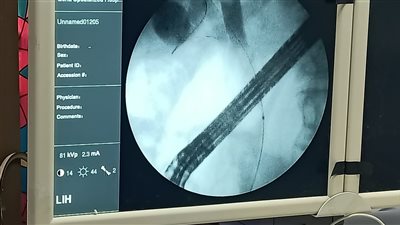

وقال شاهد على الواقعة، بعد تواصل أهل الشاب معه: “الشاب دا اسمه عبدالله، شاب محترم دخل يعمل عملية في مستشفى خاصة بالمحلة، عملية بسيطة في الأنف، وللاسف بسبب خطأ طبي الراجل حالته اتدهورت، وحرفيًا يعتبر مات، لو اتشال من علي الآجهزة، والمستشفي حاليًا طالبة من أهله مبلغ كبير جدًا، والأصعب إنهم علشان عارفين أنه خطأ، بيحاولوا يمضوا زوجته علي إقرار، بإخلاء مسئوليتهم عن اللي بيحصل”.

كما تابع عن مستجدات الواقعة: الطبيب الذي أجري الجراحة هو أ - ع، طبيب الأنف والأذن والحنجرة، وبعد اكتشاف وجود تطورات صعبة في حالة المريض، انسحب تمامًا من الأمر، وترك أهل المريض في مواجهة المستشفى".

وقال: الطبيب لا يرد على اتصالات أهل المريض، بعد علمه بتقديم شكوي ضده وضد طبيب التخدير والمستشف، وأن المستشفي استقبلت الحالة على إنها مقر فقط لإجراء العملية من جانب الطبيب، وحاليا المستشفى تحاول إنقاذ ما يمكن إنقاذه، والأهل لاحول لهم ولاقوة، خاصة وأن ظروفهم المادية لا تسمح بأي شئ، والمريض شفاه الله متزوج من فترة قريبة ولديه طفل تم ولادته قبل دخول العمليات بشهور، وأن الواقعة وصلت إلى وزارة الصحة، وقررت تشكيل لجنة عاجلة لبحث الأمر طبياً وكتابة تقرير بالواقعة".